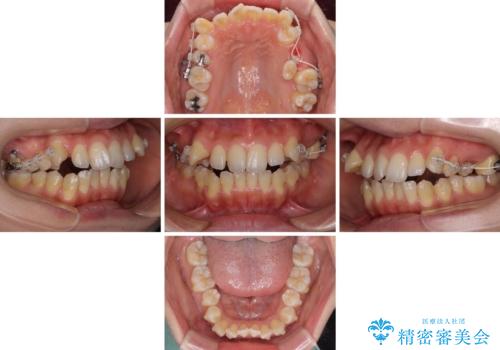

乳歯を抜歯し、舌側の永久歯を引っ張り出すこととしましたが、希望のインビザラインでは移動量が大きすぎて対応できない可能性があったため、ワイヤー装置にて改善することとしました。

ワイヤー装置にてある程度歯列が改善されたところで、上下をインビザラインにて矯正治療を行うこととしました。

舌のトレーニングをしっかりと行ってくださり、前歯部のオープンバイトは大幅に改善されました。

もう少しでよりタイトに前歯が接触できそうでしたが、患者様がもう十分とのことで治療を終了しました。